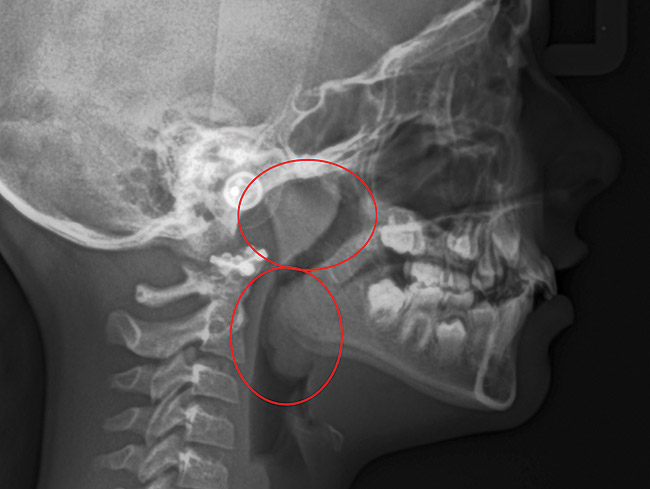

(9.) An

Figure 9

(10.) Narrow maxilla with tooth wear and bilateral crossbite.

Figure 10

(11.) Adenoidal tissue blocking the velopharyngeal airway.

Figure 11

(12.) Class II Angle classification with worn dentition and anterior open bite.

Figure 12